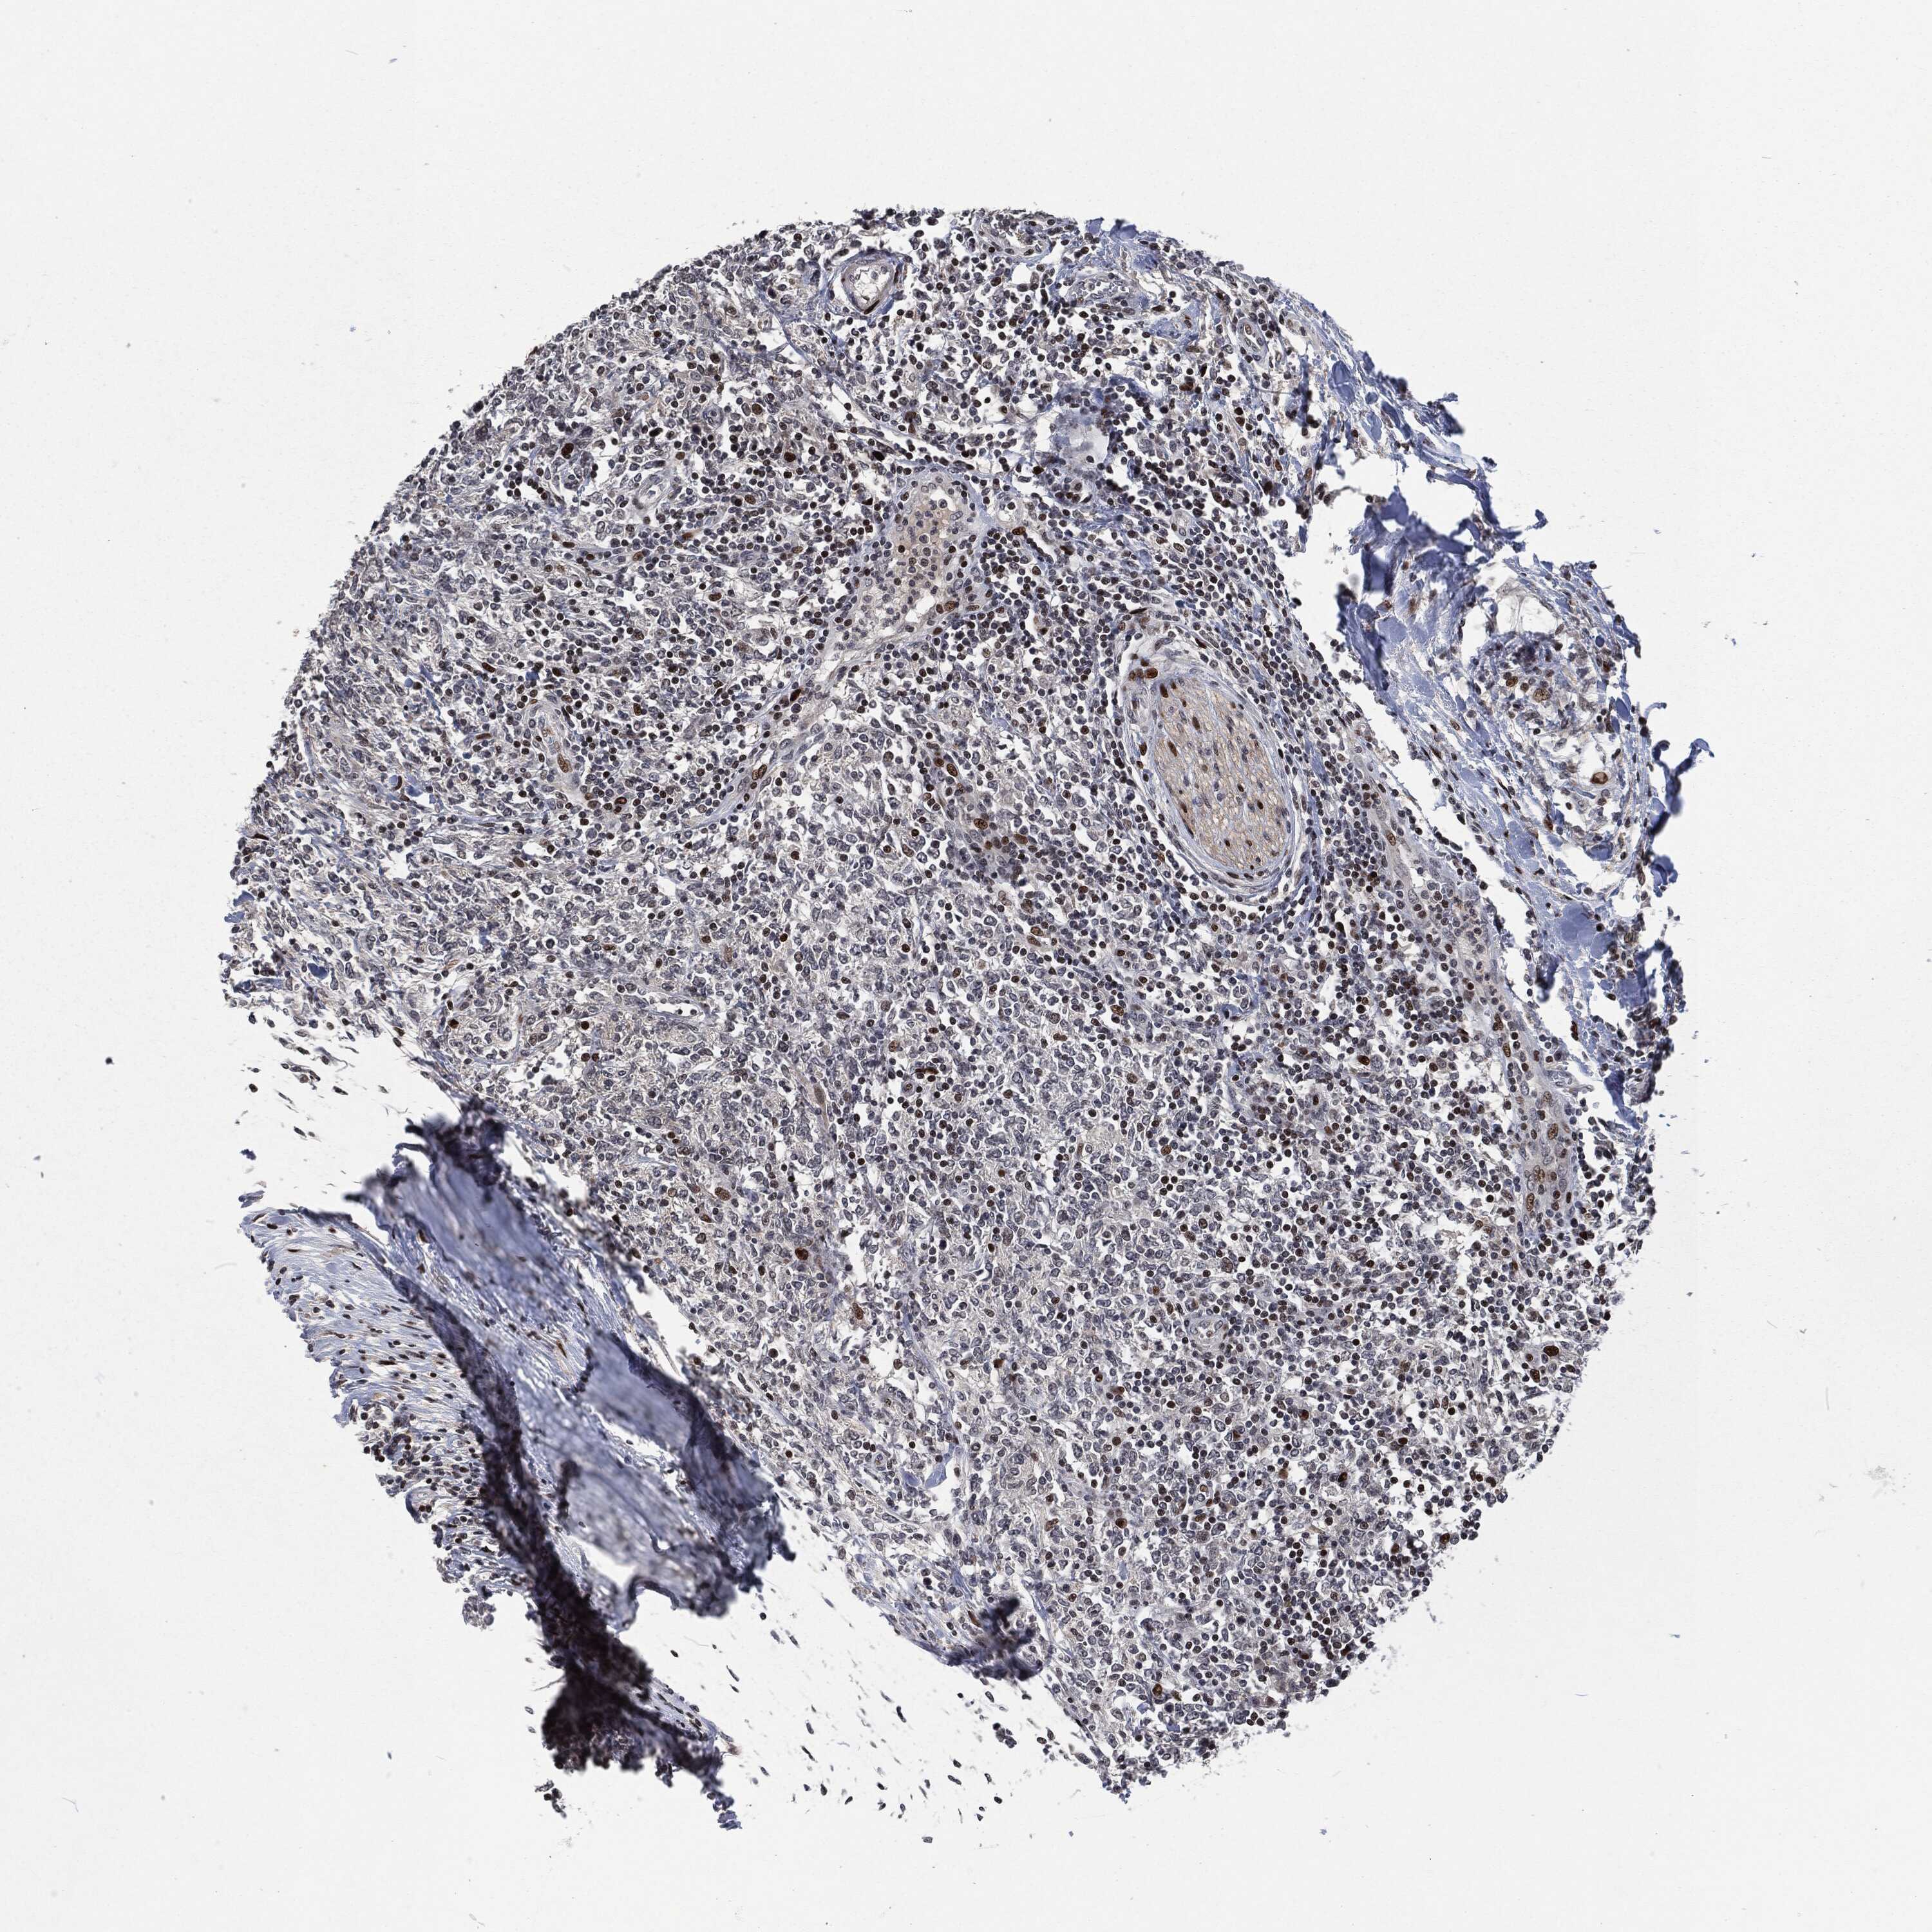

CANCER LYMPHOMA Show tissue menu

LYMPHOMA - Protein expressioni

A mouse-over function shows sample information and annotation data. Click on an image to view it in a full screen mode. Samples can be filtered based on level of antibody staining by selecting one or several of the following categories: high, medium, low and not detected. The assay and annotation is described here.

Each image is clickable and will lead to virtual microscopy that enables deeper exploration of all samples and also displays staining intensity scores, fraction scores and subcellular localization as well as patient and tissue information for each sample.

Malignant lymphoma, non-Hodgkin's type, High grade

Hodgkin's disease, NOS

Malignant lymphoma, non-Hodgkin's type, Low grade